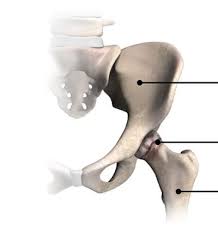

Introduction Hip pain can gradually limit your ability to move …

Introduction to Robotic Hip Replacement Robotic hip replacement in Korba …

Introduction to Robotic Hip Replacement Robotic hip replacement in Khairagarh-Chhuikhadan-Gandai …